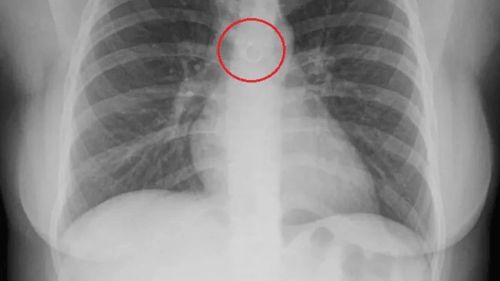

Medicina.az xəbər verir ki, bir ay öskürdükdən sonra Monika Dejanira Cabrera həkimə gedib və səbəbini öyrənəndə dəhşətə gəlib. Məlum olub ki, ağciyərində burun halqası ilişib qalıb.

Metal əşyanın aortasından cəmi 0,5 millimetr məsafədə yerləşdiyi üçün onun asanlıqla ölə biləcəyini deyiblər. Monika çox güman ki, çökmüş ağciyər və ya aorta perforasiyasından öləcəkdi.